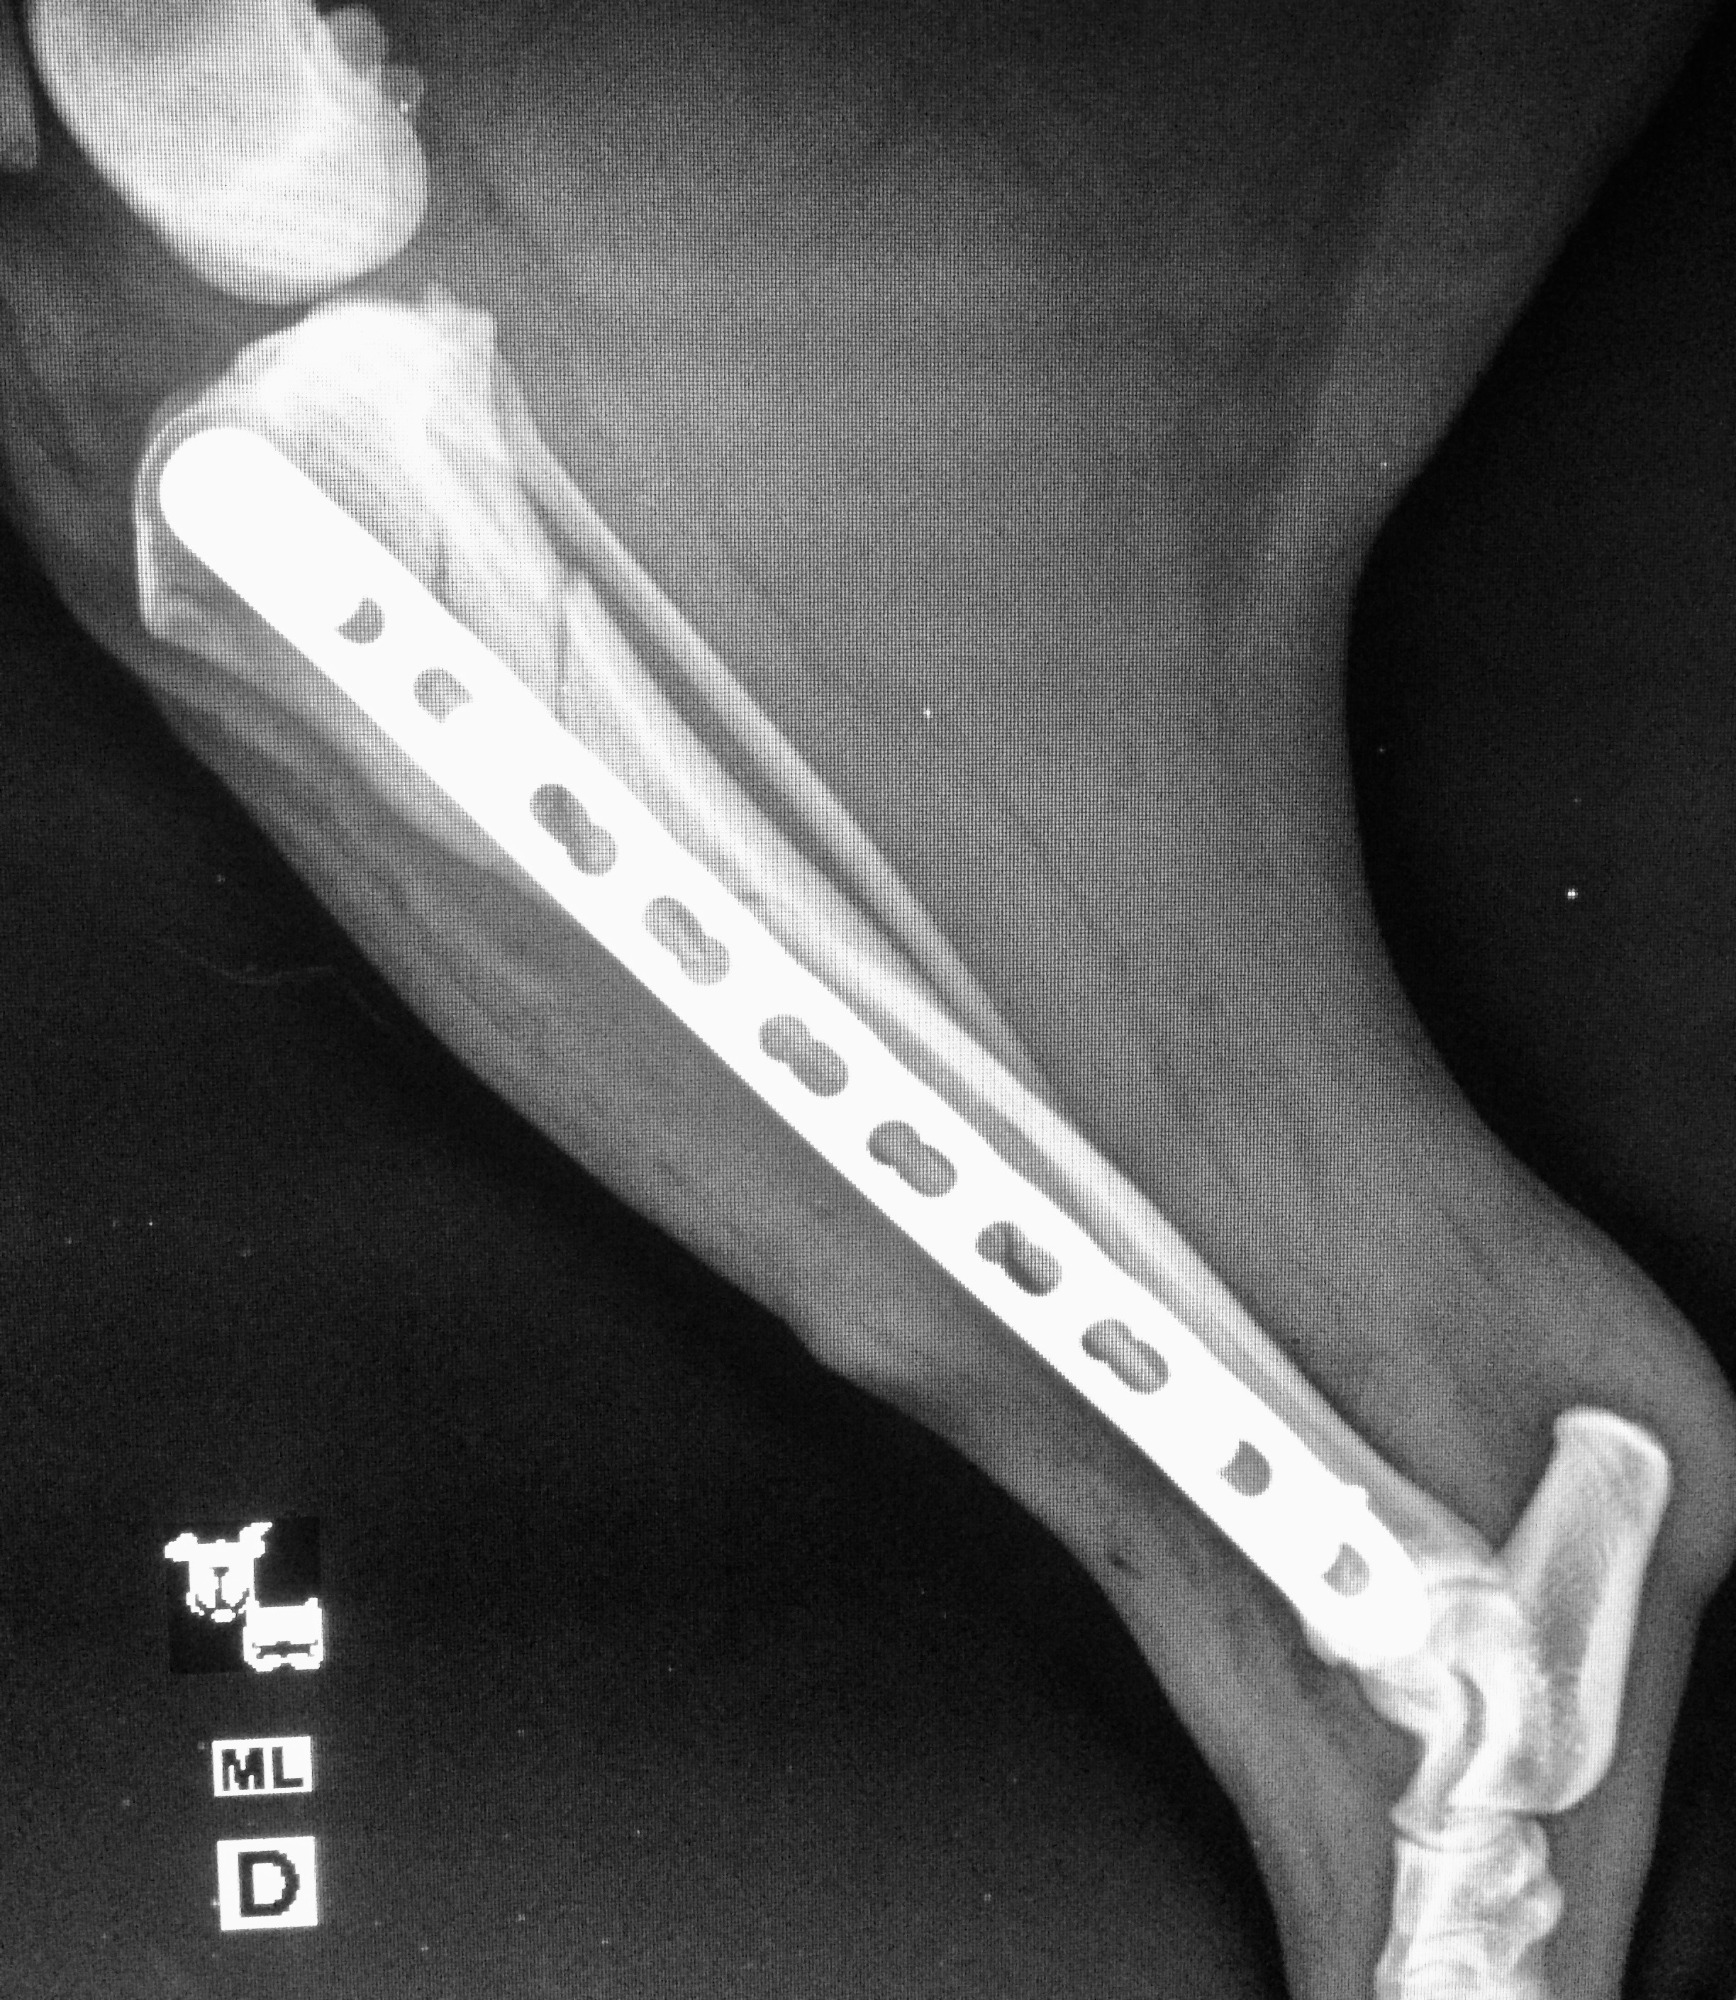

Frakturversorgung (Knochenbrüche)

Behandlung von Frakturen bei Hunden und Katzen mittels moderner Verfahren.

Ziel ist eine stabile Fixation, eine schnelle Heilung und die möglichst frühzeitige Wiederherstellung der Belastbarkeit.

Frakturversorgung mit Arthrex Implantate

Für die Behandlung von Knochenbrüchen verwenden wir moderne Implantate von höchster Qualität. Sie bieten eine sehr gute Stabilität und unterstützen eine sichere Heilung. Je nach Art der Fraktur kommen Implantate aus Titan oder hochwertigem chirurgischem Edelstahl zum Einsatz. Die Implantate sind in passenden Größen verfügbar und genau auf den Knochen und die Anatomie Ihres Tieres abgestimmt.